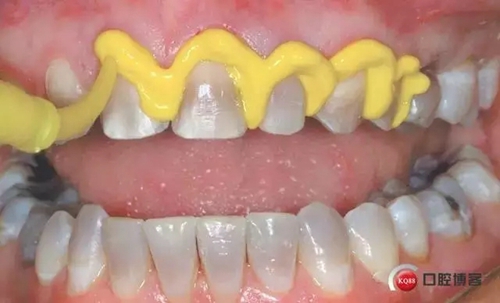

5. 放置第二根排齦線:選擇一根可以填滿牙齦溝的排齦線??梢杂^察到排齦線完全包繞牙體。第二根排齦線往往需要浸漬止血材料: 如果是通透性好的牙冠(二硅酸鋰)選擇氯化鋁止血材料;如果是不透明的冠(金屬冠/烤瓷冠)則選擇和硫酸鐵。注意: 盡管硫酸鐵有效,但是硫酸鐵可以使基牙染色,并可以使通透性好的牙冠透色。

1498612885_827290.jpg